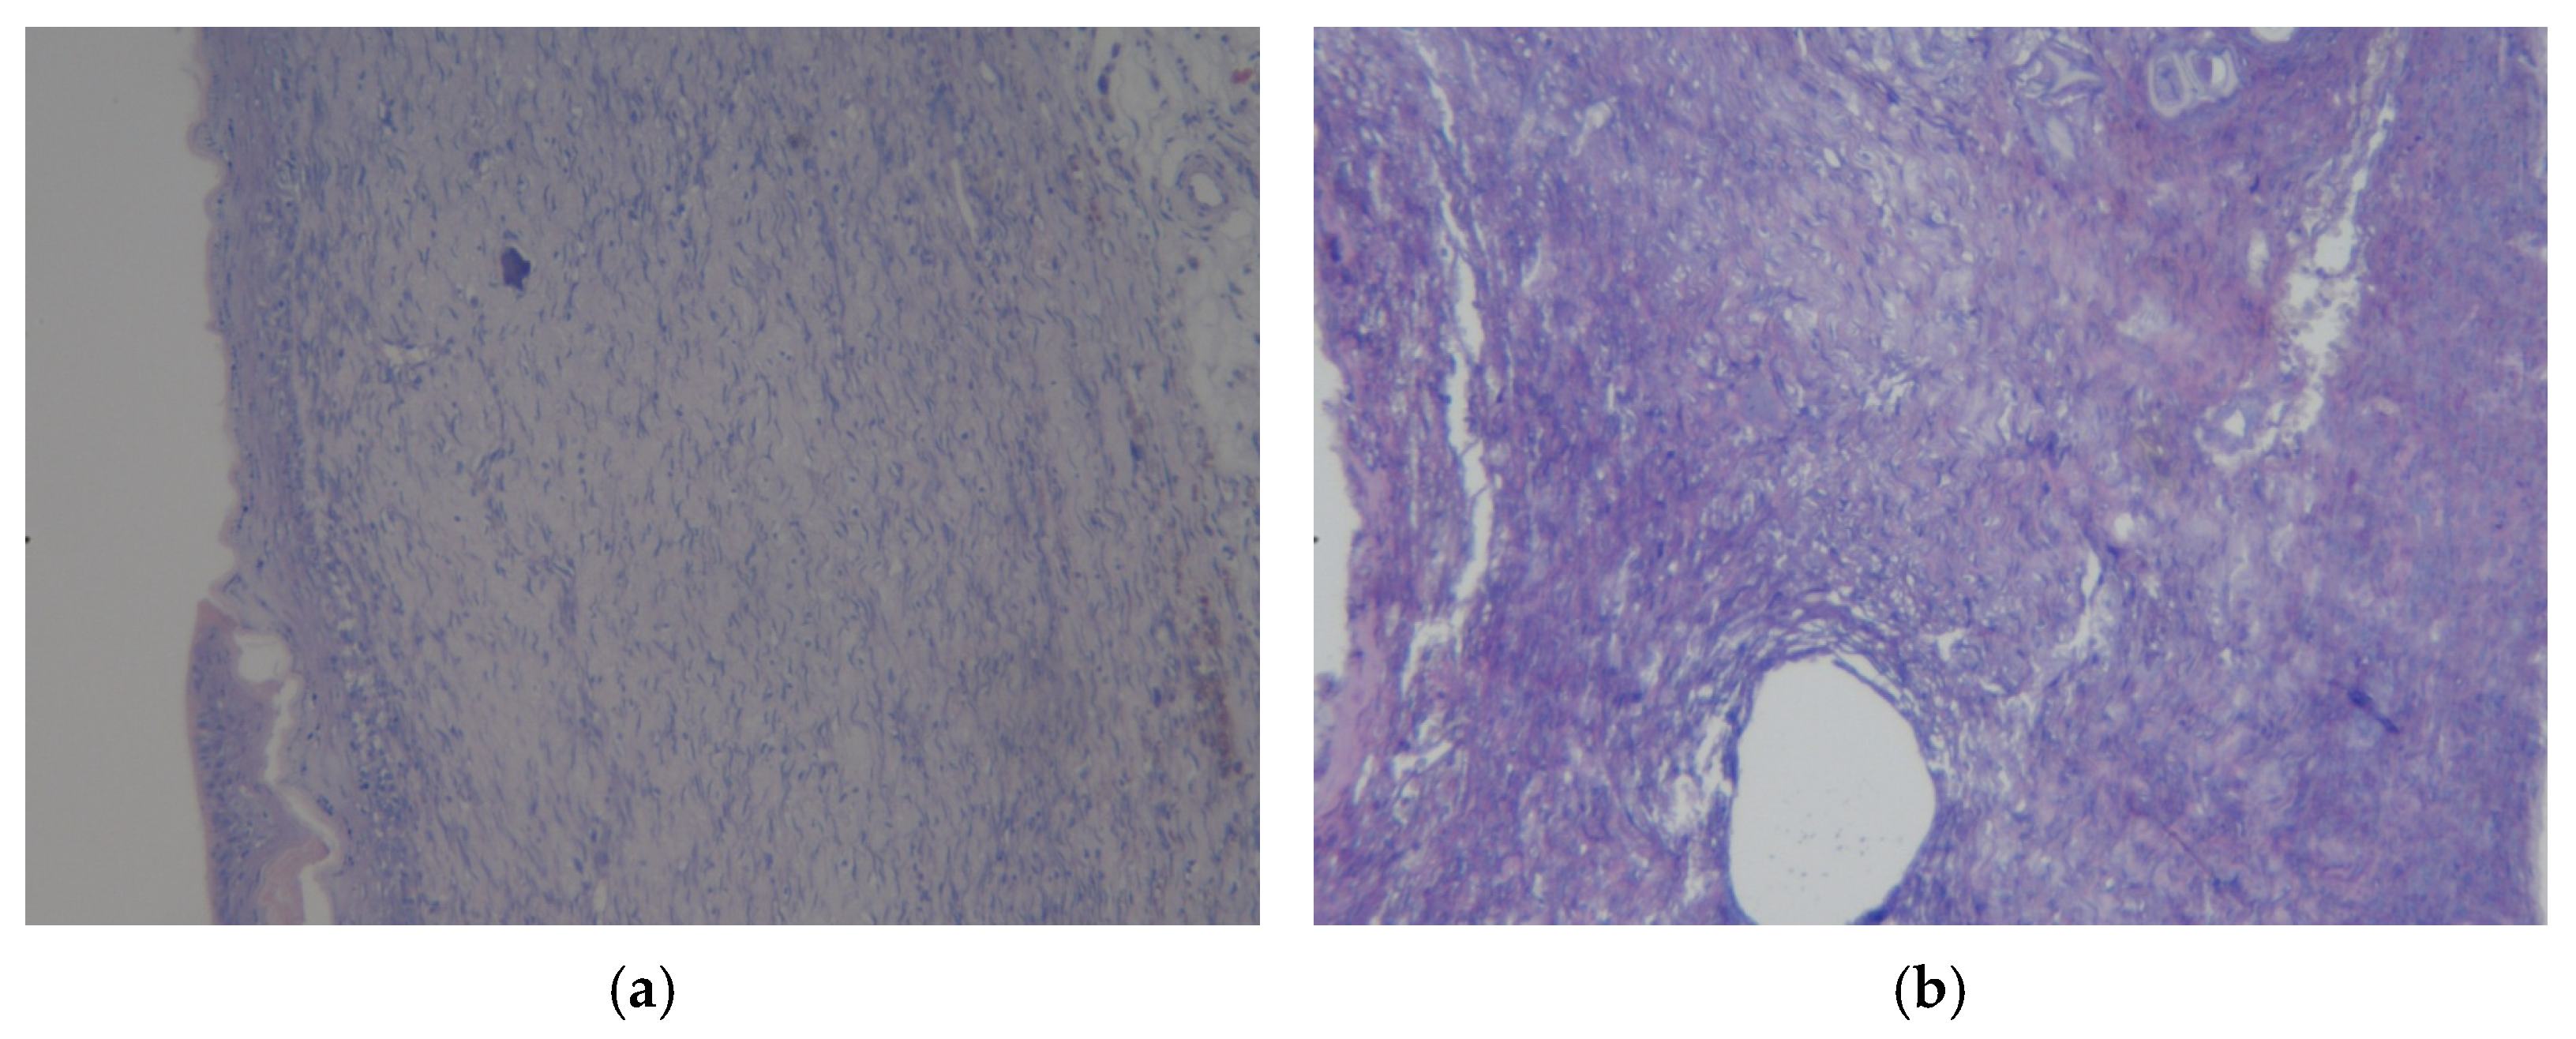

3.3. Results of Morphological Examination

3.4. Assessment of Microcirculation in the Healing Process of Burn Wounds